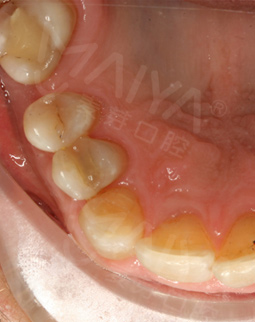

2017年3月 这里有最好的医生

戴完牙冠,无论是颜色还是咀嚼性能方面都和我的真牙一样,恢复了往日的形象也恢复了原有的咀嚼功能。种植牙手术的成功,让我拥有了更加灿烂的笑容。十年里我从来没有在中国去过任何医院看过任何医生,但是这次却在麦芽口腔见识了中国医生,和中国功夫一样,very good!这里有最棒的环境,而且这里有最好的医生!